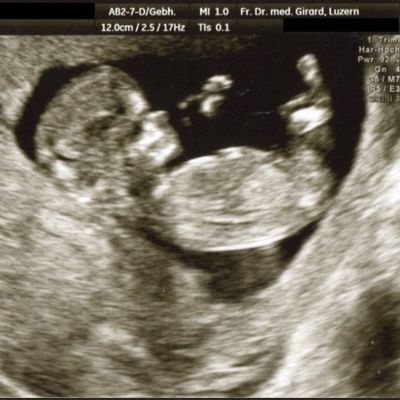

Im zweiten Trimester

(20 – 23 SSW)

können das Wachstum des Kindes und die Fruchtwasser-Menge, wichtige Hinweise auf eine normale Entwicklung des Kindes, beurteilt werden. In diesem Alter können auch schwerere Fehlbildungen erfasst werden, beispielsweise von Kopf und Gehirn, Wirbelsäule, Herz, Nieren, Magen und Extremitäten. Ebenso wird der Sitz der Plazenta beurteilt.